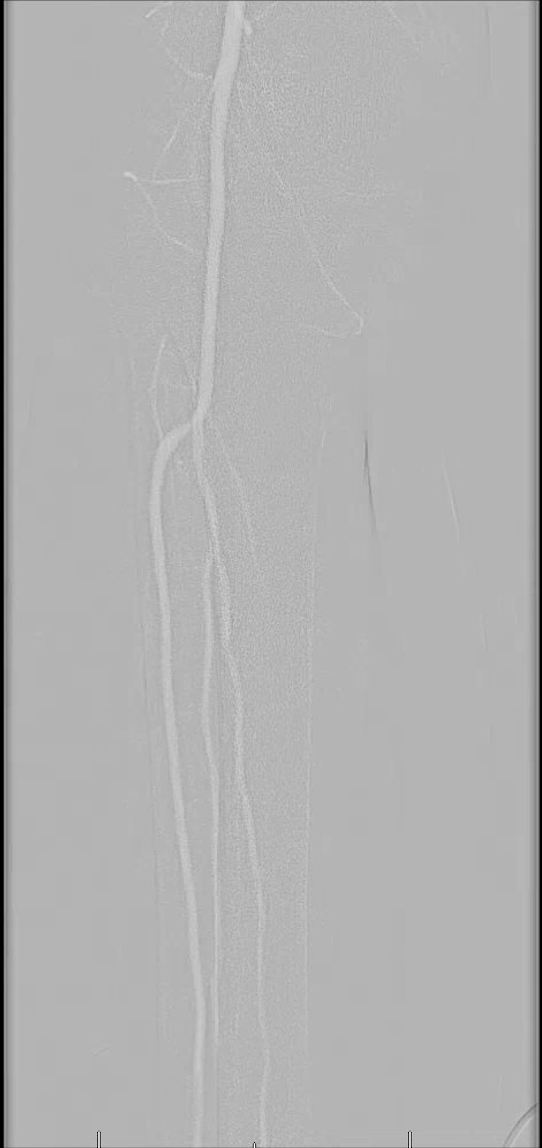

There are several unique properties of carbon dioxide that allow for its use as a contrast agent.10-12 For starters, carbon dioxide displaces the blood rather than mixing with it like an iodinated contrast. It is also less dense than surrounding bodily tissues and is therefore considered a negative contrast agent. Due to this, digital subtraction fluoroscopy is necessary to remove the surrounding anatomic structures and highlight the vascular structures while performing this technique. The vessels will appear bright on carbon dioxide angiograms whereas they appear dark using traditional methods. The gas is also buoyant, meaning it preferentially fills the anterior portion of larger blood vessels when patients are in a supine position. To improve visualization, physicians often take the feet out of the dependent position and elevate them by about 15 degrees.

One injects the carbon dioxide either manually or with an automated injector system.10-12 For the distal arteries like the leg, ankle and foot, inject a quantity of 15 to 20 mL of carbon dioxide over a span of two to three seconds. This rate is slightly faster than the flow of blood in that area. If the injection is too slow, then the vessel will not fill completely and if the injection is too fast, the gas may reflux proximal to the injection site and cause pain. In order to allow the lungs to eliminate the gas properly, several minutes should pass between injections and one should avoid excessive gas volumes.

Perhaps the greatest criticism of carbon dioxide angiography is poor image quality. Sometimes one cannot perform the procedure solely with carbon dioxide and must rely on supplemental contrast media, albeit at reduced volumes in comparison to a traditional angiogram. The distal extremities also present a unique challenge because the gas must travel the farthest distance from the injection site. However, improvements in digital subtraction angiography software and techniques have greatly improved visualization in recent years. When the carbon dioxide is injected, there may be incomplete filling of the vessel, making it appear as though there are “holes” in the image. By digitally stacking multiple areas of the same vessel segment, a more complete picture can emerge. If this does not occur, one may mistake the “holes” for areas of stenosis.19

Kusuyama and colleagues presented a case study of a 62-year-old male who had previously developed Stevens–Johnson syndrome in response to iodinated contrast.23 He required a stent of his superficial femoral artery for lower extremity pain and ulcers. A limitation of carbon dioxide angiograms is that one cannot digitally subtract stents out of the images. Therefore, it is difficult to assess if there are any residual areas of stenosis within the stent or if there has been dissection of the vessel wall from an oversized stent. The authors used intravascular ultrasound after deploying the stent to evaluate its positioning and efficacy. This technique uses an ultrasound probe on the end of the catheter wire as it is passed within the lumen of the vessel. They used 11 separate injections of 30 mL of carbon dioxide and successfully performed the intervention.